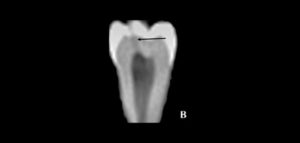

Las imágenes obtenidas mediante CBCT han asumido un papel prominente en el diagnóstico de la disfunción de la articulación temporomandibular (ATM), para la evaluación de